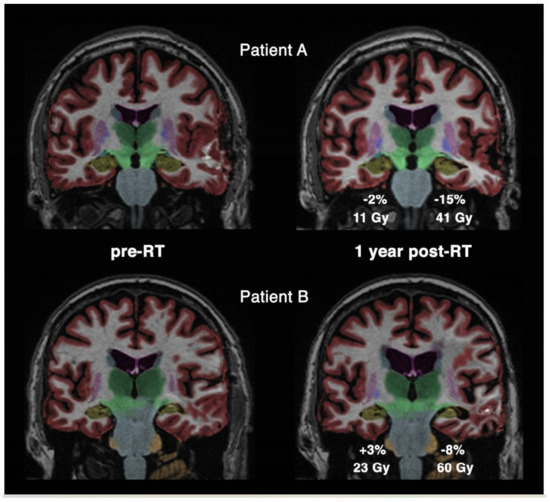

- Gommlich, A.; Raschke, F.; Wahl, H.; Troost, E.G.C. Retrospective assessment of MRI-based volumetric changes of normal tissues in glioma patients following radio(chemo)therapy. Clin. Transl. Radiat. Oncol. 2018, 8, 17–21. [Google Scholar] [CrossRef] [PubMed]

- Petr, J.; Platzek, I.; Hofheinz, F.; Mutsaerts, H.J.M.M.; Asllani, I.; van Osch, M.J.P.; Seidlitz, A.; Krukowski, P.; Gommlich, A.; Beuthien-Baumann, B.; et al. Photon vs. proton radiochemotherapy: Effects on brain tissue volume and perfusion. Radiother. Oncol. 2018, 128, 121–127. [Google Scholar] [CrossRef] [PubMed]

- Nagtegaal, S.H.J.; David, S.; Philippens, M.E.P.; Snijders, T.J.; Leemans, A.; Verhoeff, J.J.C. Dose-dependent volume loss in subcortical deep grey matter structures after cranial radiotherapy. Clin. Transl. Radiat. Oncol. 2021, 26, 35–41. [Google Scholar] [CrossRef]